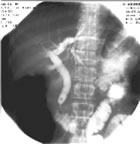

PTC 的X线特征有:

①肝总管或左右肝管昝有环形狭窄,狭窄近端胆管扩张,其中可见结石阴影;

②左右肝管或肝内某部分胆管不显影;

③左右叶肝内胆管呈不对称性、局限性、纺锤状或哑铃状扩张。CT也有重要诊断价值,特别是对于并发胆汗性肝硬化和癌变者。